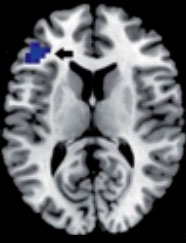

Esta “teoría dual del razonamiento” ha recibido recientemente un sólido sustento biológico a través de estudios con imágenes neurofuncionales del cerebro, que han demostrado dos patrones anatómicos diferentes de activación de áreas corticales durante los procesos de pensamiento no analítico y analítico involucrados en la toma de decisiones médicas.

Pensamiento analítico

Pensamiento no analítico

Durning SJ, Costanzo ME, Van Der Vleuten C. Functional neuroimaging correlates of thinking flexibility and knowledge structure in memory: Exploring the relationships between clinical reasoning and diagnostic thinking. Med Teach. 2015 Jun 16:1-8